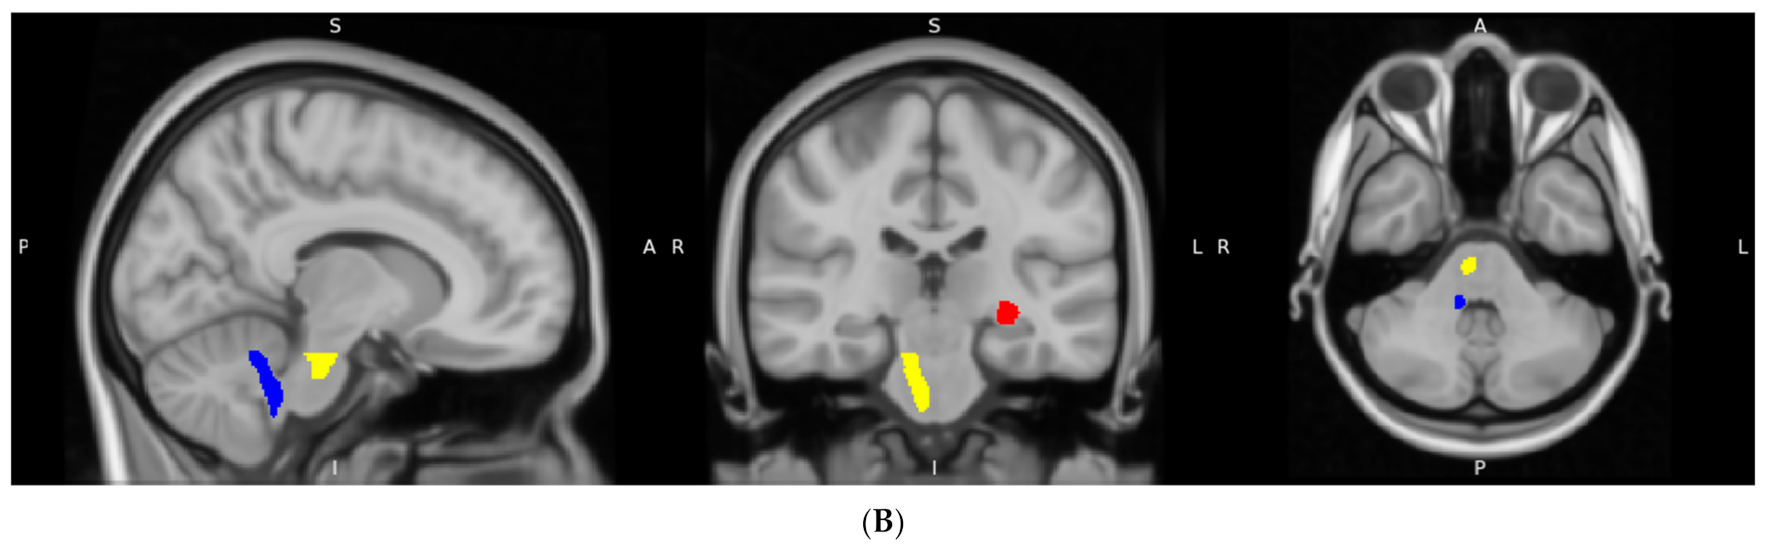

Figure 3.

WM regions with significant differences in FA and MD values. (A) regions with significant differences in FA (red: right CP; yellow: left FX/ST; blue: right FX/ST) (B) regions with significant differences in MD (red: left FX/ST; yellow: right CST; blue: right ICP).

The study also identified that the TCC group significantly differed from the control group in MD in the right corticospinal tract (CST) (F = 6.625, p = 0.014), right inferior cerebellar peduncle (ICP) (F = 6.045, p = 0.019), and left FX/ST (F = 5.070, p = 0.030) (Figure 3B). Specifically, the TCC group demonstrated lower MD values in the left FX/ST region compared to the control group. In contrast, the TCC group exhibited higher MD values in the right CST and the right ICP relative to the control group.